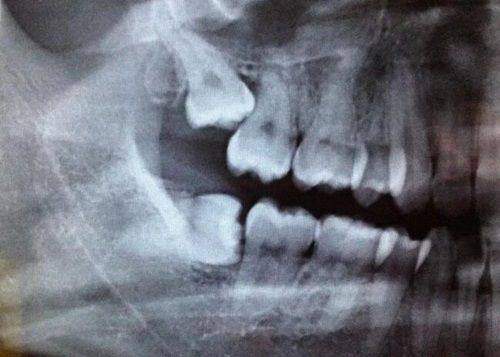

在硬件方面,诊所可能配备了精良的口腔医疗设备,如数字化X光机、全景影像机等,就像深圳阳光口腔医院一样,这些设备能提高诊断的正确率,让治疗过程更加效率高。在软件方面,诊所拥有专精的医师团队,他们具备扎实的口腔理论知识,不断进行技术培训和学术交流,能够为患者提供专精的口腔健康服务。同时,诊所建立了完善的服务体系,提供一对一的询问服务,医护人员热情周到,随时关注患者的需求,让患者在就诊过程中感受到舒适和安心。